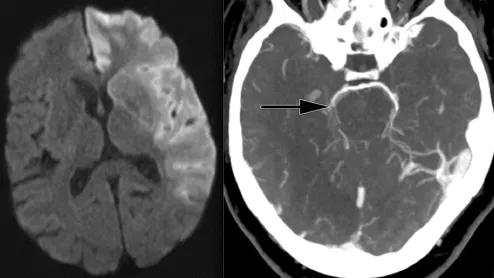

Ischemic stroke CT imaging. Images courtesy of RSNA

Despite increases of 250% for CTA and 428% for CTP, researchers observed lower rates of neuroimaging utilization among rural residents, older individuals (80 years and above), women and Black patients.